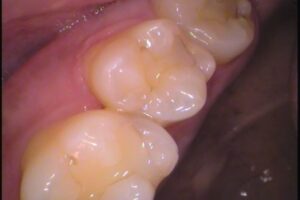

虫歯の例を見てみましょう。

歯と歯の間の虫歯です。どこに虫歯があるか分かりますでしょうか?

虫歯の所を削ってみてみると・・・

歯と歯の間の中に茶色い虫歯がありました。

これは分かりませんね。